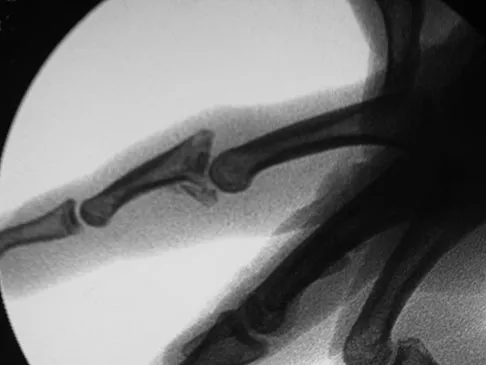

A 16-year-old high school pitcher notes acute pain on the medial side of his elbow during a pitch. Examination that day reveals medial elbow tenderness, pain with valgus stress, mild swelling, and loss of extension. Plain radiographs show closed physes and no fracture. Which of the following diagnostic studies will best reveal his injury?

Figures 42a and 42b shows the radiographs of a 20-year-old man who sustained a hyperextension injury to his little finger. Multiple attempts at closed reduction have been unsuccessful. Management should now consist of